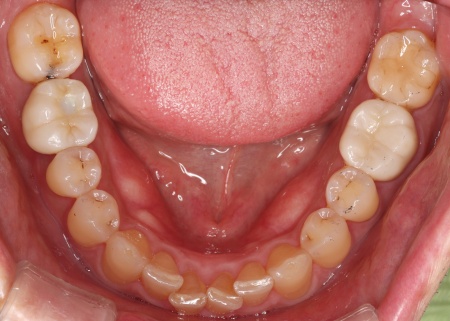

治療前